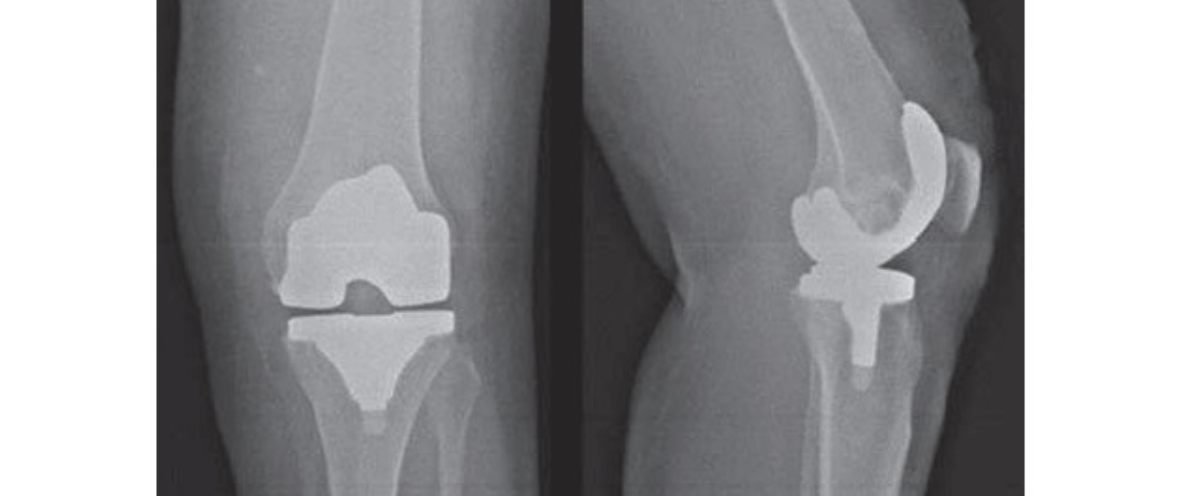

Artroplastia Total de Joelho

• Sentar no leito logo que possível (pode ser no 1º dia)

• Sentar fora do leito no 2º dia e em pé sem carga

• Antibioticoprofilaxia

• Profilaxia TEV no 1º dia

• Dreno de sucção por 48 horas. Se débito > 400 mL/12h, avisar ortopedista

• Retirar enfaixamento apenas se estiver sujo

• Exercícios isométricos

• Exercícios de movimentação do membro inferior e quadril no 2º dia

• Retirar SVD no 2º dia

OBS: podem receber alta já no segundo dia se clinicamente estável, e avisar ortopedista